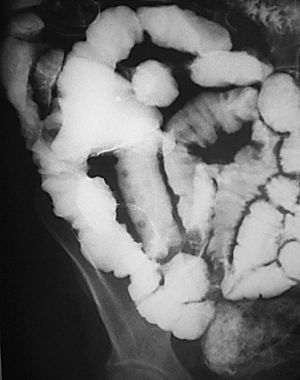

En la fase activa hay presencia de úlceras superficiales o aftoides (fig. 4). Pueden evolucionar haciéndose ulceraciones fisurantes longitudinales y transversales, dejando entre sí islotes de mucosa normal, constituyendo el concepto de patrón en "empedrado" (fig. 5).

Fig. 4.--Enfermedad de Crohn, fase activa inflamatoria. (A) En el estudio baritado, a nivel de íleon distal se observan pequeñas imágenes puntiformes de cúmulo de bario rodeadas de un halo de edema, que corresponden a úlceras superficiales o aftoides. (B) Correlación endoscópica.

Fig. 5.--Enfermedad de Crohn, fase activa inflamatoria. (A) Ulceraciones longitudinales y transversales que dejan entre sí islotes de mucosa edematosa, constituyendo el patrón en "empedrado" en el estudio baritado. (B) Correlación microscópica: ulceración fisurante rodeada del infiltrado inflamatorio, lesión claramente delimitada y rodeada de mucosa normal.